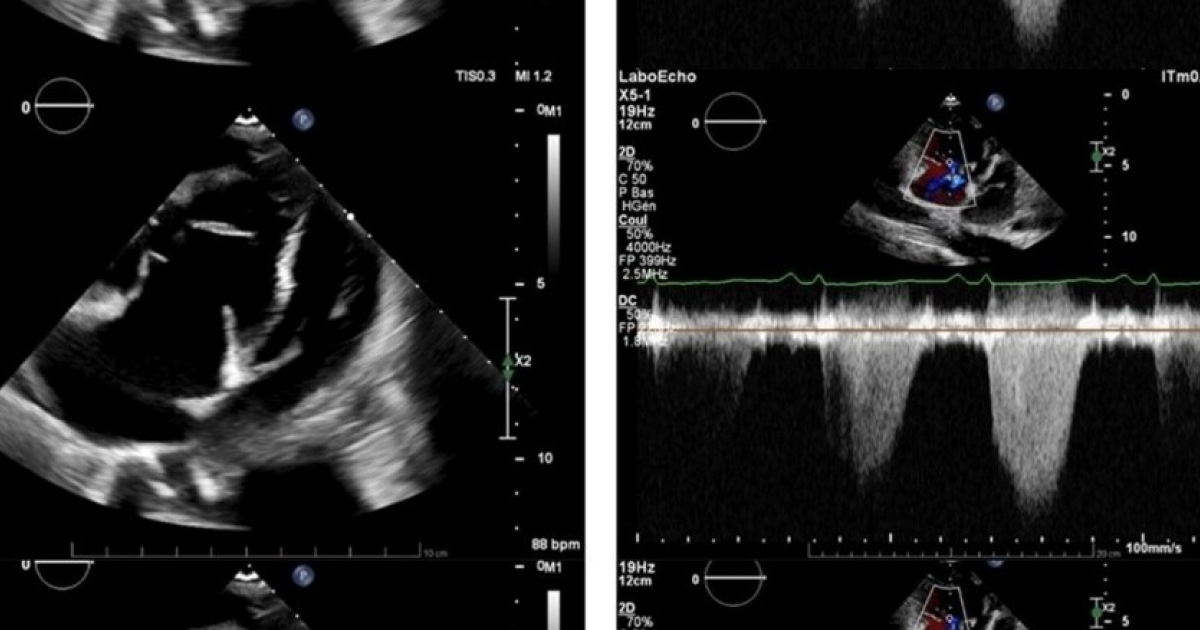

Цинга привела к легочной гипертензии у швейцарки

Швейцарские врачи описали случай легочной гипертензии, которая развилась на фоне крайнего дефицита витамина C — цинги. По-видимому, она развилась из-за длительного расстройства пищевого поведения, которое привело к крайнему истощению. Лечение с помощью витаминных добавок и мочегонных привело к быстрому улучшению состояния. Случай описан в BMJ Case Reports....